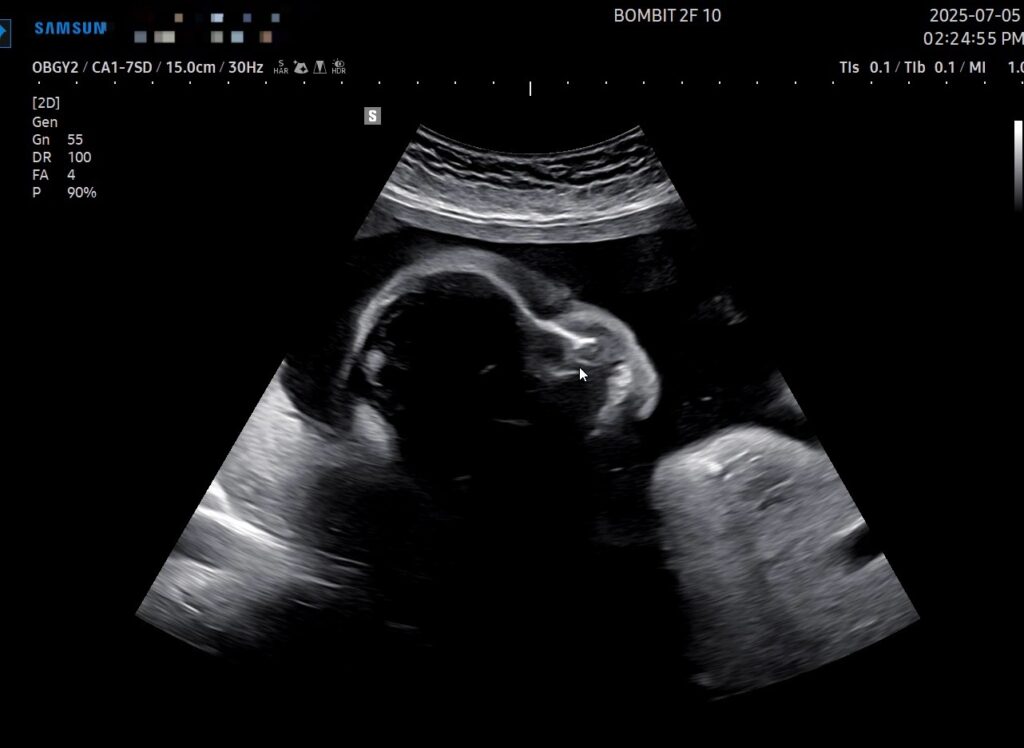

이건 초음파 사진!

초기 때는 초음파 옆모습 단면이 아기처럼 예쁘게 보였는데, 전반적인 크기가 커지면서 눈두덩이랑 턱뼈가 초음파로 적나라하게 드러나게 되었다. 그래서 초음파 사진이 약간 괴기스러워졌다..ㅋㅋㅋ